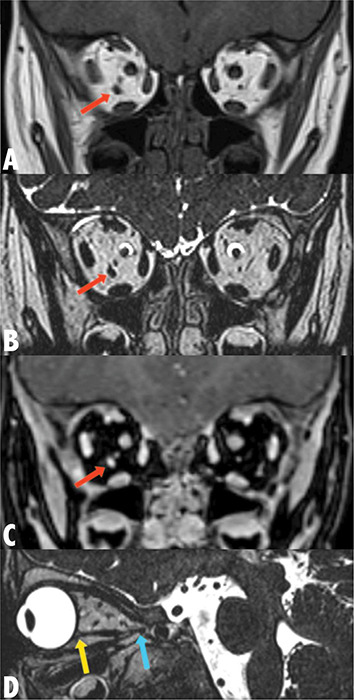

教学要点:副眼外肌是少见的眶内先天性结构,可引起复视和限制性斜视。

Teaching point: Accessory extraocular muscles are rare intraorbital congenital structures that can cause diplopia and restrictive strabismus.